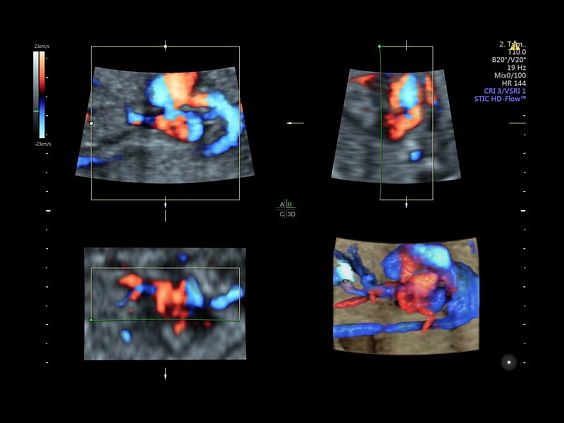

• Advanced STIC - расширенный программный пакет для исследования сердца плода в режиме 4D для механических и электронных объемных датчиков:

• Использование цветного, энергетического допплера, В Flow - режим STIC.

• Сочетание с М-режимом - STIC-M-Mode

• Перемещаемый источник света - STICflow

• SonoVCADHeart - программное обеспечение для исследования сердца плода в режиме 3D/4D (быстрый доступ к плоскостям сканирования) по рекомендациям ISUOG

• HDlive Flow Silhouette - режим "Силуэт" с выделением границ полостей сердца и сосудов, совместимый с визуализацией кровотока